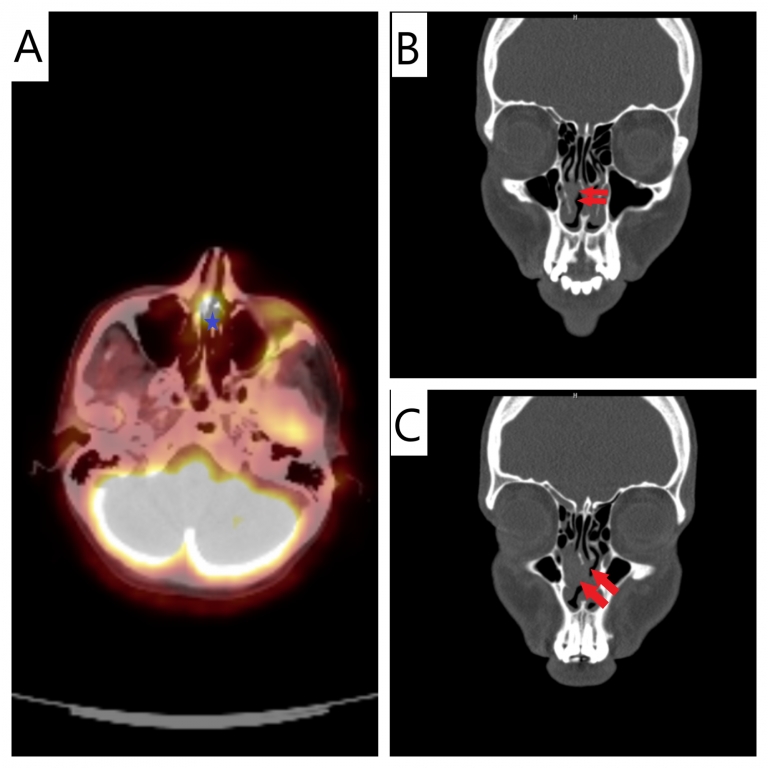

Turkish abstractEkstramedüller plazmositom, kemik iliği dışındaki yumuşak dokularda görülen nadir bir plazma hücreli neoplazmdır. Nazal kavite yerleşimli ekstramedüller plazmositom, tüm baş-boyun tümörlerinin %1’inden azını oluşturur ve genellikle 40 yaş üzerindeki bireylerde görülür. Bu sunumda, 28 yaşındaki kadın hastada nazal ekstramedüller plazmositom tanısı ve tedavi süreci paylaşılmıştır. Hasta, sağ nazal kavitede tıkanıklık ve epistaksis şikayetleriyle başvurmuş, yapılan görüntüleme ve biyopsi sonucunda kappa monoklonal plazma hücreli neoplazm saptanmıştır. Serum protein elektroforezi, kemik iliği biyopsisi ve PET-BT ile multipl miyelom dışlanmıştır. Histopatolojik olarak CD138 pozitifliği ve yüksek Ki-67 düzeyi saptanmış, bu bulgular doğrultusunda nazal ekstramedüller plazmositom tanısı netleştirilmiştir. Tedavi olarak radyoterapi planlanmıştır. Ekstramedüller plazmositom tanısı, multipl miyelomdan ayırt edilmesi açısından dikkatli sistemik değerlendirme gerektirir. Nazal ekstramedüller plazmositom yüksek lokal kontrol oranlarıyla iyi prognoz sunsa da lokal nüks ve multipl miyeloma dönüşüm riski nedeniyle uzun dönem takip önemlidir.IntroductionEkstramedüller plazmositom (EMP), kemik iliği dışında yumuşak dokularda ortaya çıkan, monoklonal plazma hücrelerinin proliferasyonu ile karakterize nadir plazma hücreli neoplazmdır. EMP, sistemik bir hastalık olan multipl miyelomdan (MM) ve kemik iliğinde ortaya çıkan soliter kemik plazmositomundan farklılık gösterir. Nazal EMP ise son derece nadir görülmekle birlikte plazma hücreli tümörlerin ve baş-boyun malignitelerinin küçük bir bölümünü oluşturur. Tüm plazma hücreli tümörlerin yaklaşık %3 ila %5'ini [1] ve tüm baş-boyun tümörlerinin yalnızca %1'inden azını oluşturmaktadır [2]. Nazal EMP tipik olarak orta ve ileri yaşlardaki bireyleri etkiler; başlangıç yaşı genellikle 40 ila 70 yaş arasındadır [3]. 40 yaşın altında görülmesi nadirdir [4]. Bu vaka sunumunda 28 yaşında bir hastada görülen nazal EMP tanı ve tedavi süreci paylaşılacaktır. Case Report28 yaşında kadın hasta yaklaşık 2 haftadır sağ nazal kaviteden nefes alma güçlüğü ve ara ara olan burun kanaması şikayeti nedeniyle kulak burun boğaz polikliniğine başvurdu. Hastanın alınan anamnezinde çölyak hastalığı nedeniyle takipte olduğu öğrenildi. Yapılan fizik muayenede sağ nazal kavitede orta konkadan köken aldığı düşünülen vasküleritesi artmış kitle izlendi.

DiscussionEMP, yumuşak dokularda ortaya çıkan, monoklonal plazma hücrelerinin çoğalması ile oluşan nadir bir lokalize plazma hücreli neoplazmdır. Soliter EMP, oldukça nadir görülmekte olup insidansı 100.000 kişide 0.04 olarak bildirilmektedir [5]. EMP'nin kesin tanısı, MM gibi sistemik tutulumun ekartasyonu ile konulur. Bu özellikler arasında kemik iliği tutulumunun olmaması (genellikle %10'dan az plazma hücresi), normal kemik taraması ve anemi, hiperkalsemi veya böbrek yetmezliği gibi MM ile ilişkili sistemik komplikasyonların bulunmamasıdır [6]. Nazal EMP son derece nadir bir tanı olmakla birlikte tüm baş-boyun tümörlerinin %1'inden azını oluşturmaktadır [7]. Tanı anındaki yaş, ortalama 55 ila 65 yaş arasında bildirilmektedir [8]. Erkek-kadın oranları 3:1 ila 4:1 arasında bildirilmektedir [7]. Nitekim, hastamız 28 yaşında olup literatürde bildirilen yaş aralığının oldukça altında idi. Nazal EMP'nin klinik prezentasyonu genellikle yavaş seyirli olup semptomlar genellikle nonspesifiktir [9]. En sık bildirilen semptomlar arasında genellikle tek taraflı olan nazal obstrüksiyon ve epistaksis yer alır [7]. Bizim hastamızda da başvurudan 2 hafta öncesinde başlayan burun tıkanıklığı ve epistaksis şikayeti mevcuttu. Fizik muayenede, nazal kavitede yumuşak doku kitlesi ve yüzeyel vaskülarite nedeniyle kitle manipülasyona bağlı olarak kolaylıkla kanayabilir [7]. Bu görünüm nedeniyle benign inflamatuar poliplerinden ayırtedilmesine yardımcı olabilir. Nazal EMP'nin kesin tanısı, biyopsi ile histopatolojik ve immünohistokimyasal tanı ile konur. Mikroskopik bulgular tipik olarak monoklonal plazma hücrelerinin yoğun bir infiltrasyonunu gösterir [6]. Tanı bazen plazmasitik farklılaşma görülen B- hücreli lenfomalar ve reaktif inflamatuar süreçler ile karıştırılabilir bu yüzden alanında uzman hemopatolog tanının netleştirilmesine yardımcı olur [10]. İmmünohistokimyasal (İHK) boyama, plazma hücrelerinin monoklonal doğasını doğrulamak ve EMP'yi diğer lenfoid neoplazmlardan ayırmak için vazgeçilmez bir araçtır. EMP'deki tümör hücreleri tipik olarak CD138 gibi plazma hücre belirteçleri için pozitif boyanma gösterir [7]. Bizim de hastamız da CD 138 diffüz olarak boyanma göstermiştir. (Resim 3) Nazal EMP'nin görüntüleme özellikleri, non spesifiktir. [ ]Bununla birlikte, görüntüleme, lokal evrelemede ve tümörün yayılımını belirlemek içim yardımcı olabilir [11]. Hastamızda görüntüleme olarak paranazal BT tercih edildi. Orta konka ile bağlantılı lokal opasite oluşturan kitlesel görünüm haricinde bir bulgu görülmedi. EMP’nin, MM'nin başlangıç belirtisi olabilme veya MM’ye ilerleyebilme potansiyeli göz önüne alındığında, yaygın hastalığı kesin olarak dışlamak için kapsamlı bir sistemik değerlendirme zorunludur [12]. Bu sistematik test bataryasında serum protein elektroforezi, idrarda Bence-Jones proteini, kemik tutulumunu dışlamak için PET-BT, kemik iliği ilfiltrasyonu dışlamak için ise kemik iliği aspirasyon biyopsisi yapılması gerekir. Kapsamlı sistemik değerlendirme sadece tanısal değil, aynı zamanda uzun vadeli tedavi stratejisini etkileyen kritik bir prognostik belirleyicidir. Bu kapsamlı değerlendirme, hastanın uzun vadeli yönetimini doğrudan etkiler. Yıllar sonra oluşabilecek transformasyon göz önüne alındığında bazı tanısal belirteçler hastalığın seyri hakkında kritik bir başlangıç noktası olduğunu göstermektedir [13]. Nitekim hastamıza da bu kapsamlı değerlendirme uygulanmış olup tetkiklerde MM destekler bir bulguya rastlanmamıştır. Fakat hastalığın başlangıç yaşının genç olması ve histopatolojik olarak incelenen dokuda yüksek ki-67 skoru nedeniyle MM transformasyonu için yakın takip için hasta bilgilendirilmiştir. Tedavi de radyoterapi, yüksek radyosensivitesi nedeniyle ilk tedavi yöntemi olarak kabul edilmektedir.[ ]Çalışmalar, sadece RT ile %90-95'i aşan lokal kontrol oranları bildirmektedir [14]. Cerrahi müdahale nazal EMP yönetimindeki rolü tartışmalıdır. Küçük, lokalize lezyonlarda tam cerrahi eksizyon önerilmektedir [12]. Hastamızın tedavisinde literatürle uyumlu olarak kitle lokalizasyonuna radyoterapi planlanmıştır. Nazal EMP'nin prognozu genellikle iyidir.[ ]Ancak, lokal nüks ve MM’ye transformasyon riski mevcuttur. Lokal nüks oranları %10 ila %30 arasında değişmektedir [12]. MM transformasyonu %10 ila %35 arasında bildirilmektedir [4]. ConclusionNazal EMP, genel olarak nadir görülen bir plazma hücreli neoplazmdır. EMP'nin prognozu genellikle iyi olsa da, lokal nüks ve MM’ye ilerleme riski nedeniyle uzun vadeli ve titiz takip zorunludur. Nadir de olsa, tek taraflı burun kitleleri ile başvuran hastalarda ayırıcı tanıda akılda bulundurulmalıdır. Hastalığın tanı ve tedavi süreci multidisipliner bir yaklaşımı gerektirmektedir. Informed ConsentHastanın kendisindenReferences